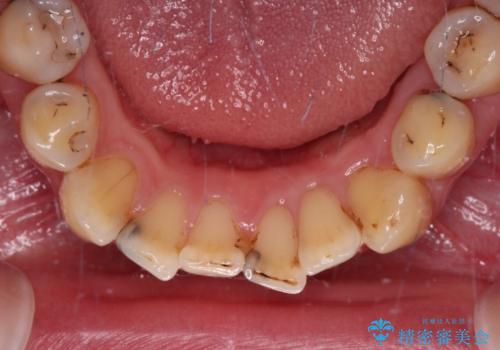

- 上下前歯や奥歯の虫歯治療を希望して来院された患者様です。

全顎的にむし歯が多く、根管治療の必要奥歯や、審美的に気になっている前歯を中心にオールセラミッククラウンにて補綴治療を行うこととしました。